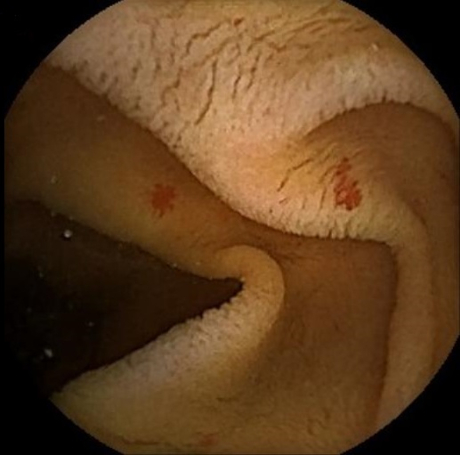

[Figure caption and citation for the preceding image starts]: Endoscopic (device-assisted enteroscopy) image of small bowel angiodysplasia after treatment with argon plasma coagulationFrom the personal collection of Dr Elli, Milan, Italy; used with permission [Citation ends].

Angiodysplasia is visualised as bright red lesions, 5-10 mm in diameter, with a branching surface network of fine, ectatic blood vessels arising from a central vessel. In hospitalised patients with acute lower gastrointestinal bleeding, the American College of Gastroenterology and European Society of Gastrointestinal Endoscopy recommend a non-urgent inpatient colonoscopy, as re-bleeding may be missed if an urgent colonoscopy is performed.[35][38]